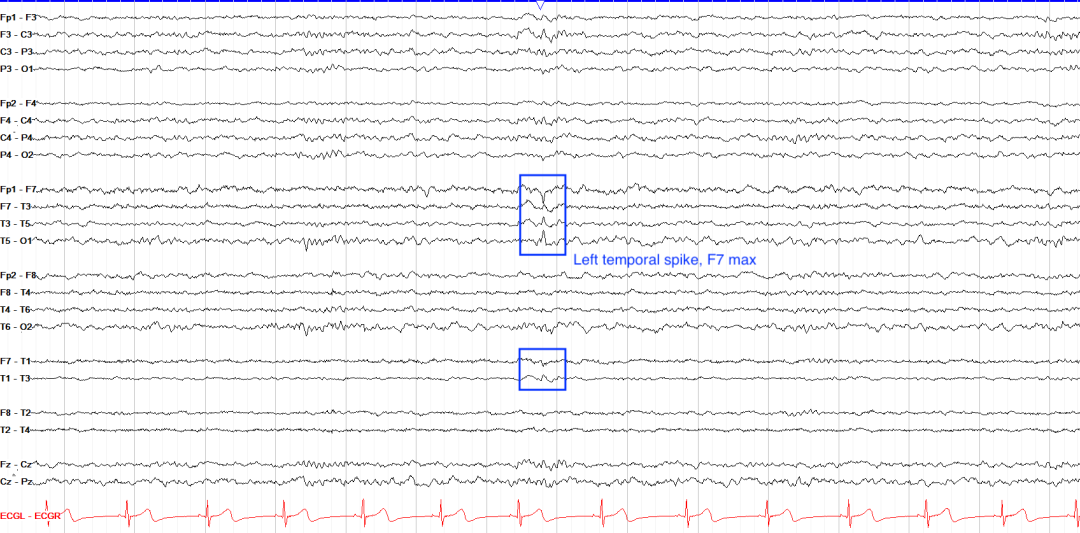

1.颞叶癫痫(Temporal Lobe Epilepsy, TLE)

波形特征:

前颞棘波:70-200 ms尖波,F7/F8或T1/T2导联显著,睡眠激活(图3A)。

发作期:4-7 Hz节律性θ活动,逐渐扩散至同侧或对侧。

临床关联:海马硬化或肿瘤常见,常伴自主神经症状或口咽自动症。